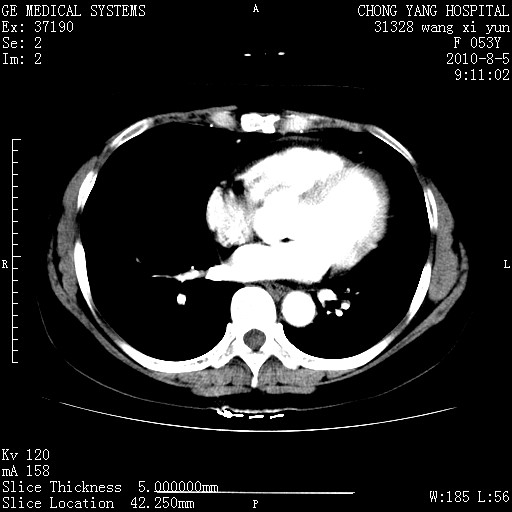

胆管细胞ca?

1)考虑肝左叶胆管细胞癌。2)脂肪肝。

支持胆管细胞ca。